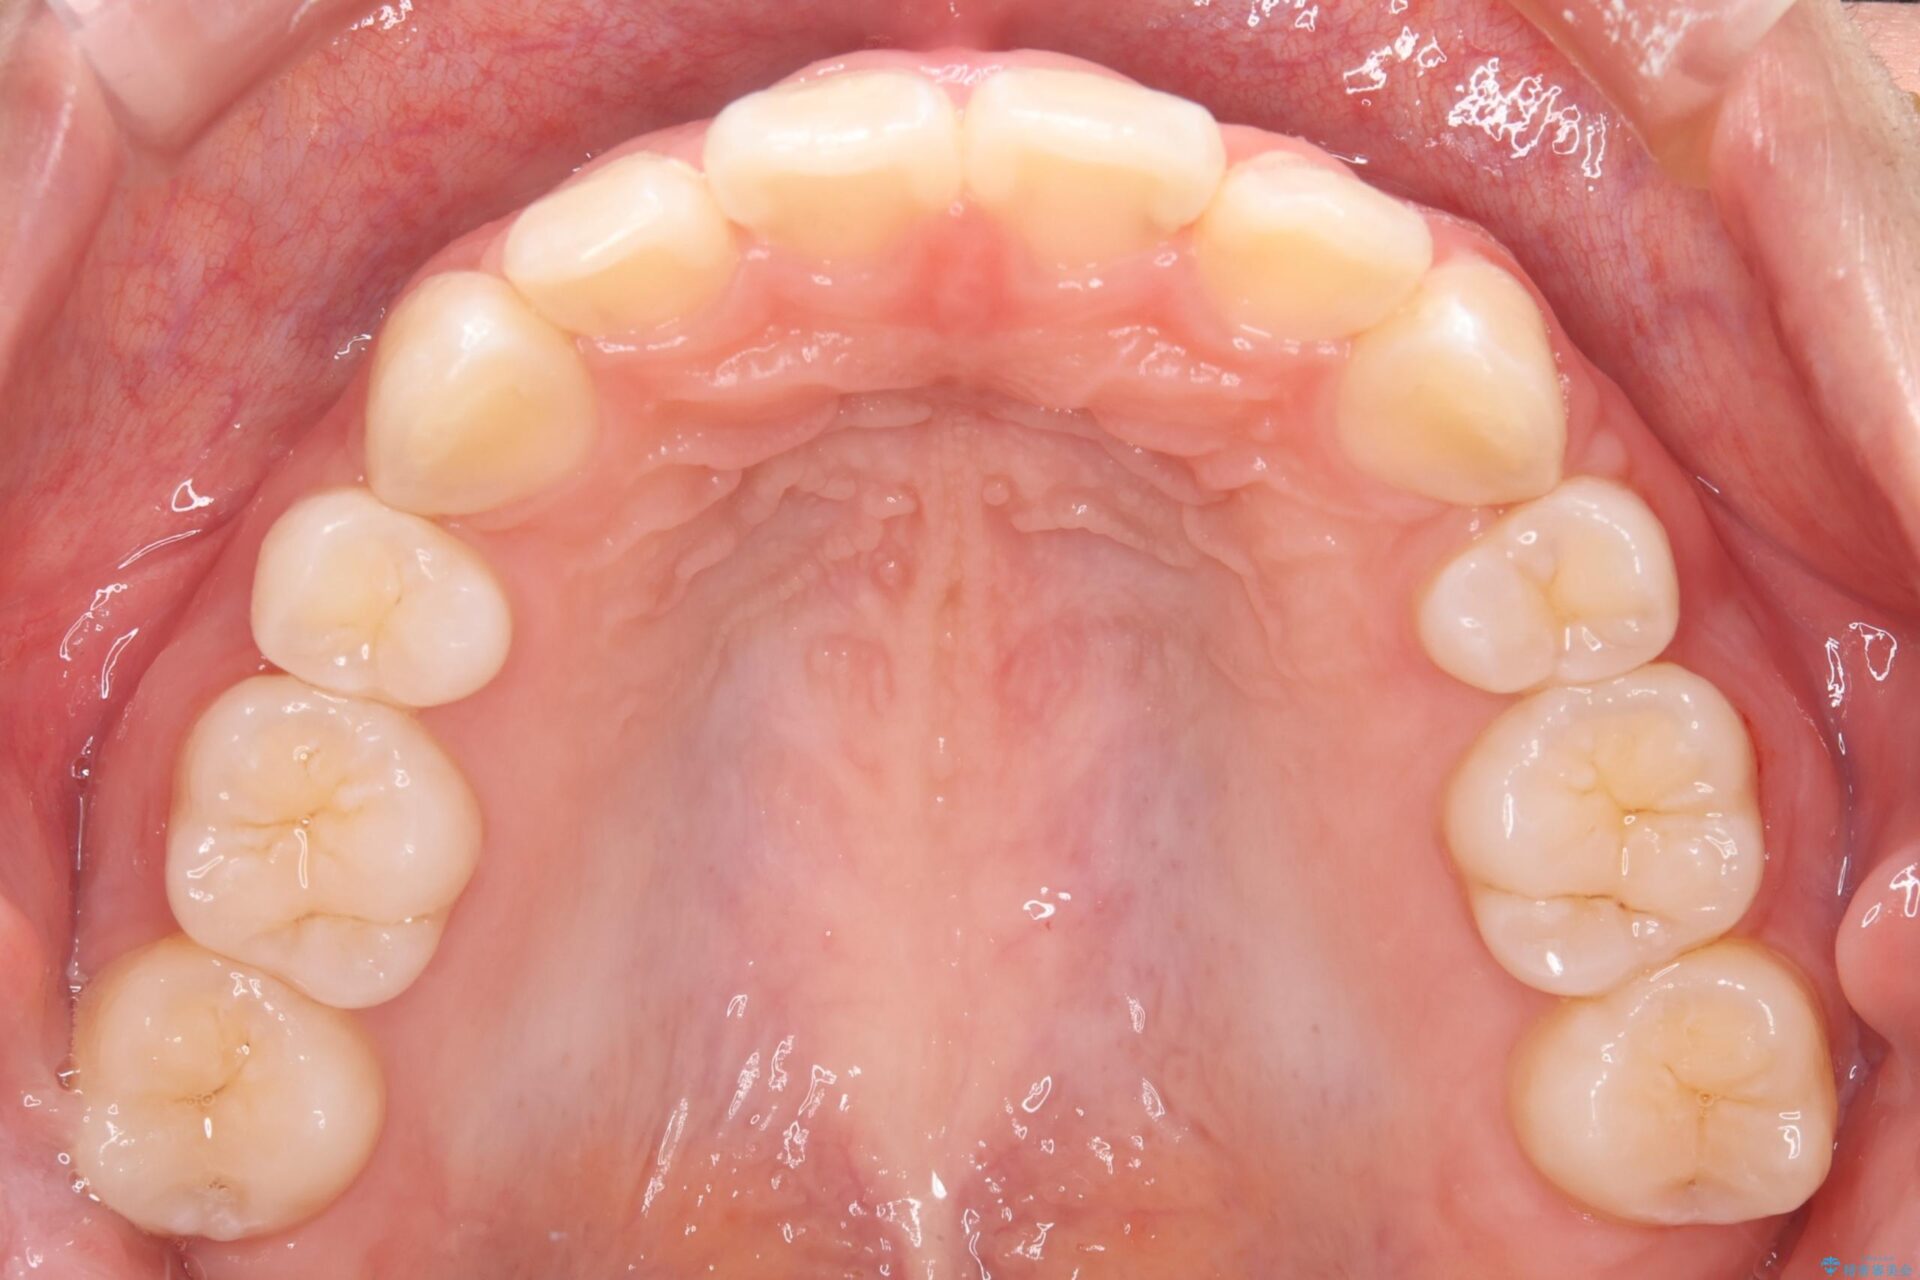

抜歯矯正で口元を下げたことで、Eラインが大変綺麗になりました。

期間も1年9ヶ月と比較的短期間で治療完了することができました。